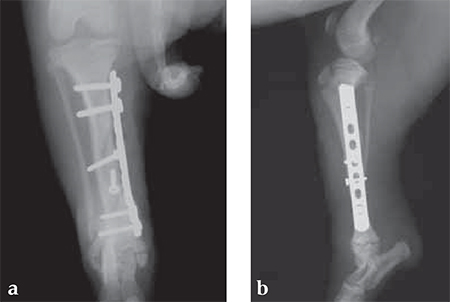

The Mini LC-DCPs and LCPs are designed for long-bone fractures in small breed dogs and cats.

The mini LC-DCPs and LCPs utilize the standard LC-DCP and locked plate design with a few minor changes. The plates feature the standard toe nail design for MIPO at one end of the plate.

The outermost hole opposite to the toe nail plate extremity was changed from either a combination hole to a stacked combination hole (Mini LCP) or from a DCU hole to a round hole. This design change allows for placement of the plate as close to the joint as possible, similar to the 3.5 mm LCPs for veterinary indications. These iterations facilitate minimally invasive plate placement as well as treatment of metaphyseal fractures. Additionally, the plates are thicker and stronger to withstand the greater loads seen in comminuted fractures in noncompliant animal patients. The plates retain the characteristic grooved undersurface for limited contact and more uniform stiffness.

A 12-week-old Yorkshire Terrier, 1.3 kg

(Case provided by Alessandro Piras, Banbridge, Northern Ireland)

Small Bones, Small Plates: Clinical Application of Mini LCP